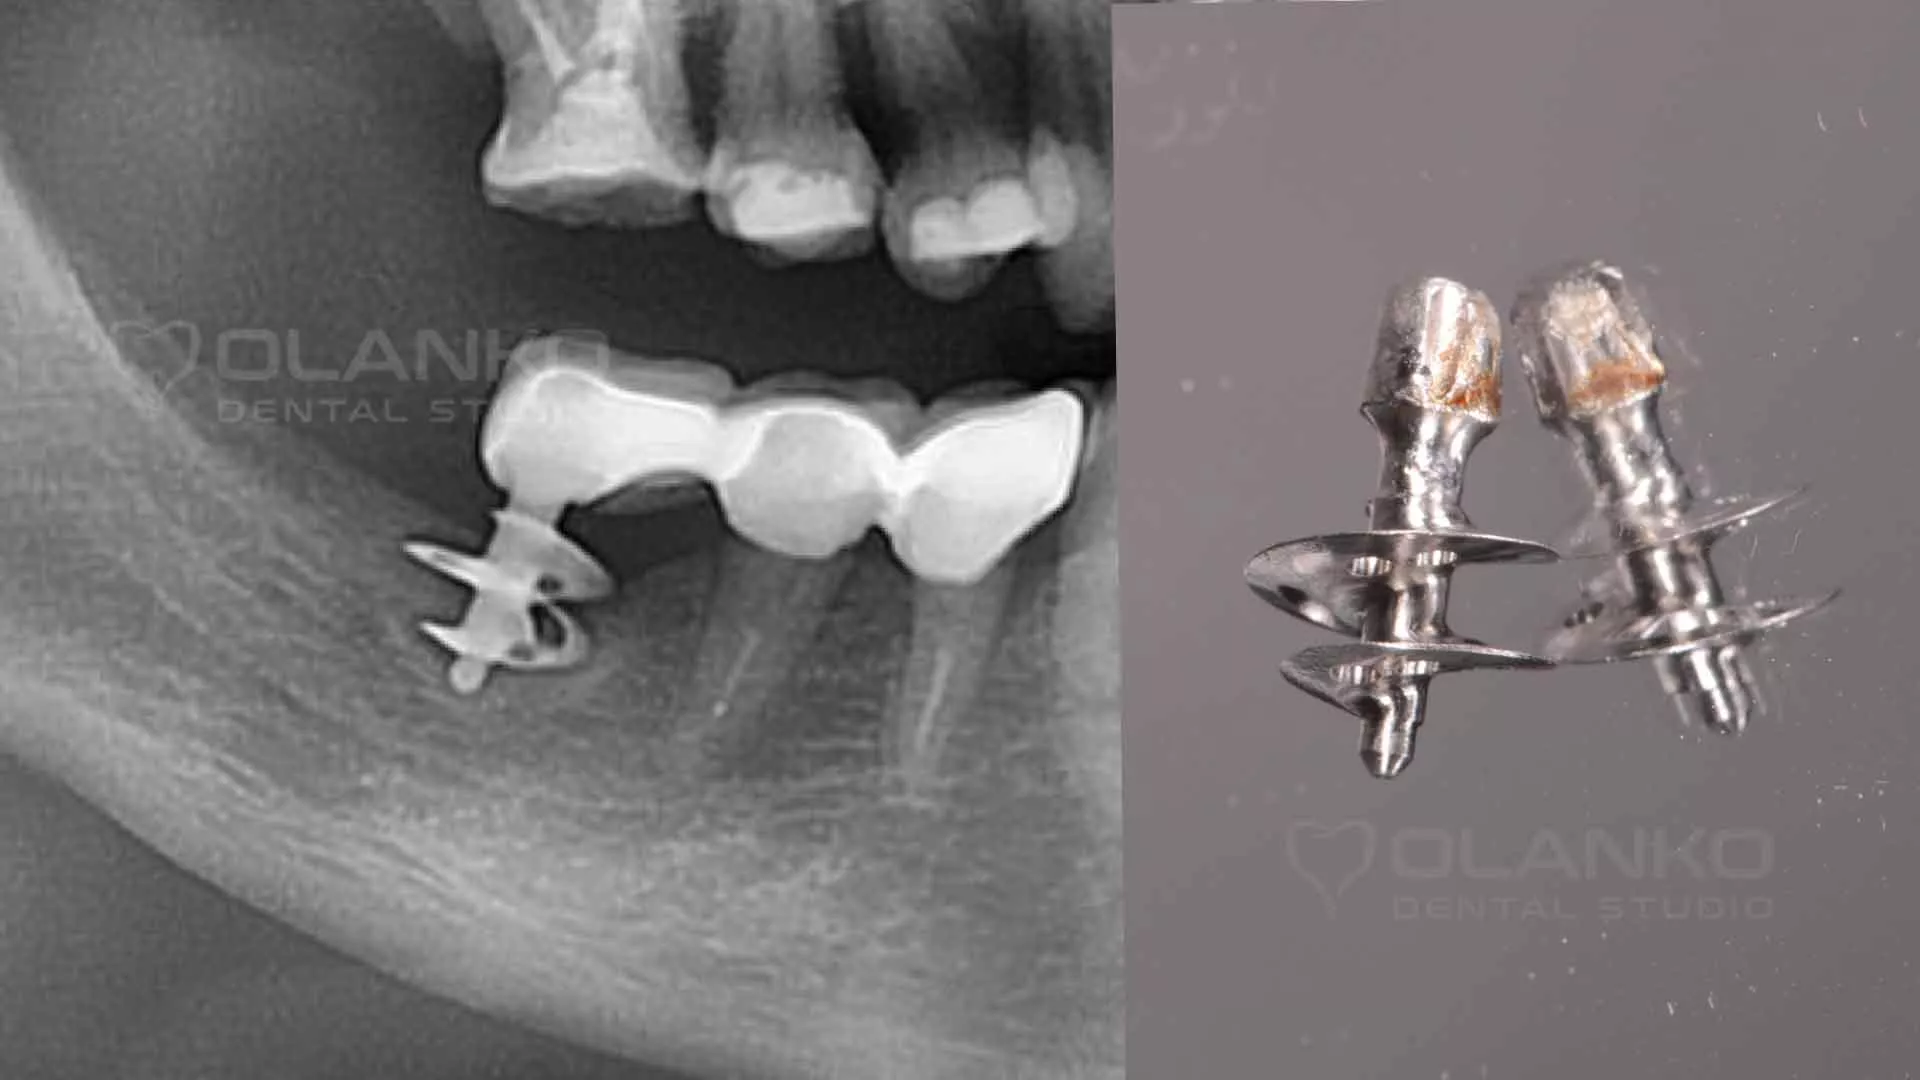

5. На месте отторжения такого протеза часто возникают большие костные дефекты. Многочисленные фото базальной имплантации показывает, как может произойти отторжение протеза.

Фото пример удаленного базального имплантата в следствии отторжения через 2 года после установки